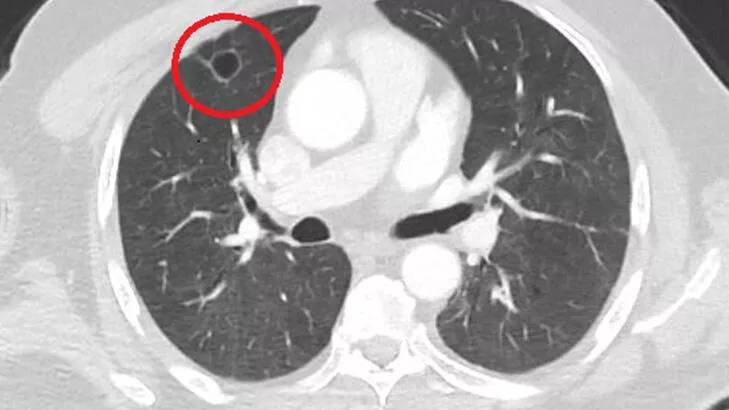

Kahramanmaraş'ta akciğer kanseri teşhisi koyulan ve ameliyata girmeden önce COVID-19 testi yapılan N.T'nin(52), aslında akciğer kanseri olmadığı anlaşıldı. Bununun nedeni ise COVID-19 virüsünün, akciğer kanserini taklit etmesiydi. Sütçü İmam Üniversitesi Sağlık Uygulama ve Araştırma Hastanesi Göğüs Cerrahi Ana Bilim Dalı Öğretim Üyesi Dr. Fatoş Kozanlı, yaşanan olayın dünya tıp literatüründe bir ilk olduğunu belirtti.Göğüs ağrılarıyla hastaneye giden N.T'nin tomografisinde sağ akciğerinde 4 santimetrelik bir tümör tespit edildi. Kanser olabileceği şüphesiyle yapılan ileri tetkikler sonrası N. T.'ye akciğer kanseri teşhisi kondu ve acil ameliyat kararı verildi. Bunun üzerine N.T., ameliyat için memleketi Kahramanmaraş'a geldi. Sütçü İmam Üniversitesi Sağlık Uygulama ve Araştırma Hastanesi Göğüs Cerrahi Anabilim Dalı Öğretim Üyesi Dr. Fatoş Kozanlı da tomografi ve test sonuçlarına göre N. T.'ye akciğer kanseri teşhisi koydu ve ameliyat yapılması gerektiğini söyledi.

"Hastamız, çalıştığı başka bir kentte göğsünden darbe alıyor ve ağrıları geçmeyince bir üniversite hastanesine başvuruyor. Burada hastaya bir akciğer grafisi çekiliyor. Sağ akciğerinde bir kitleye rastlanıyor. Daha sonra hastaya, bir akciğer tomografisi çekiliyor ve göğüs cerrahisi için önemli büyüklükte olan 4 santimetre çapında, akciğer kanserine benzer özellikte radyolojik bulgular olan bir kitle tespit ediliyor. Daha sonra hastaya yapılan ileri tetkiklerde akciğer kanseri teşhisi konuluyor. Hastaya bir cerrahi planlanıyor. Hasta Kahramanmaraşlı olduğu için kendi memleketine gelmeyi tercih ediyor. Bize başvurdu ve göğüs ağrısı şikayeti vardı. Öksürük, nefes darlığı, balgam çıkarma, ateş gibi şikayetleri yoktu. Hastayı biz de değerlendirdik ve ameliyat olmasına karar verdik. Çünkü akciğer kanserine çok benzer radyolojik bulguları vardı. Sağlık Bakanlığımızın kuralları gereği her hastayı ameliyat öncesi PCR testi yapılır. Biz de ameliyat gecesi hastadan PCR testi aldık ve testi pozitif geldi. Ameliyatımızı 14 gün erteledik ve hastamıza koronavirüs tedavisi uygulandı. Hasta 14'üncü gün tekrar bize başvurdu ve yapılan PCR testi negatif çıktı. Yeni bir tomografi çektik ve tümörün tamamen ortadan kalktığını gördük. Şimdi sonuç bilgilerinden başlangıca gittiğimizde, bu bir akciğer kanseri olsaydı, ortadan kalkması mümkün değildi. Başka bir patolojiye bağlı durum olsaydı, yine verdiğimiz tedaviyle ortadan kalkmasını çok beklemeyiz. Antiviral tedavisi verdik ve hastanın radyolojik bulguları neredeyse tamamen normale döndü. Hastaya bunu izah ettik, 'Dünya literatüründe hiç görülmeyen bir radyolojik bulgu' diyerek. Bu gördüğümüz manzara artık hastanın akciğer grafisinde yok, akciğer kanseri değil. "